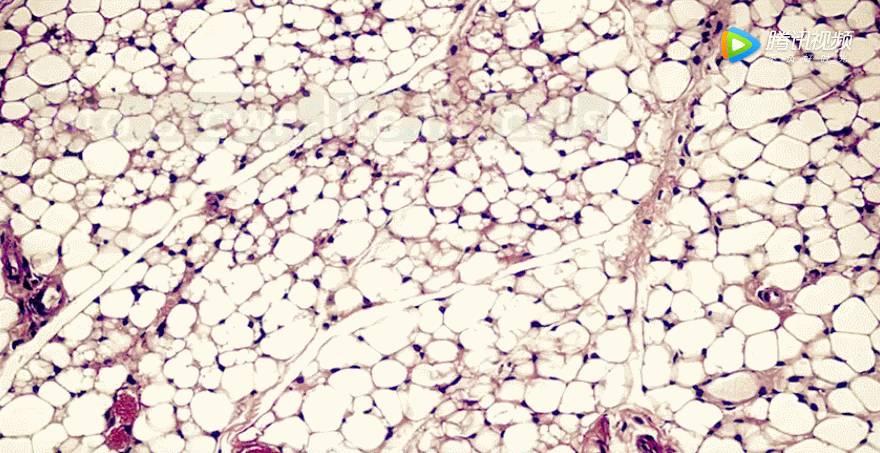

人体的脂肪有白色脂肪和棕色脂肪两种

其中白色脂肪是储存热量的

它能够将人体中多余的能量

储存起来以备不时之需

同时也是赘肉的罪魁祸首

而棕色脂肪则是耗能储热的

它可以通过燃烧引发肥胖的白色脂肪

将其转化成二氧化碳、水和热量

加快人体新陈代谢

从而达到减肥的作用